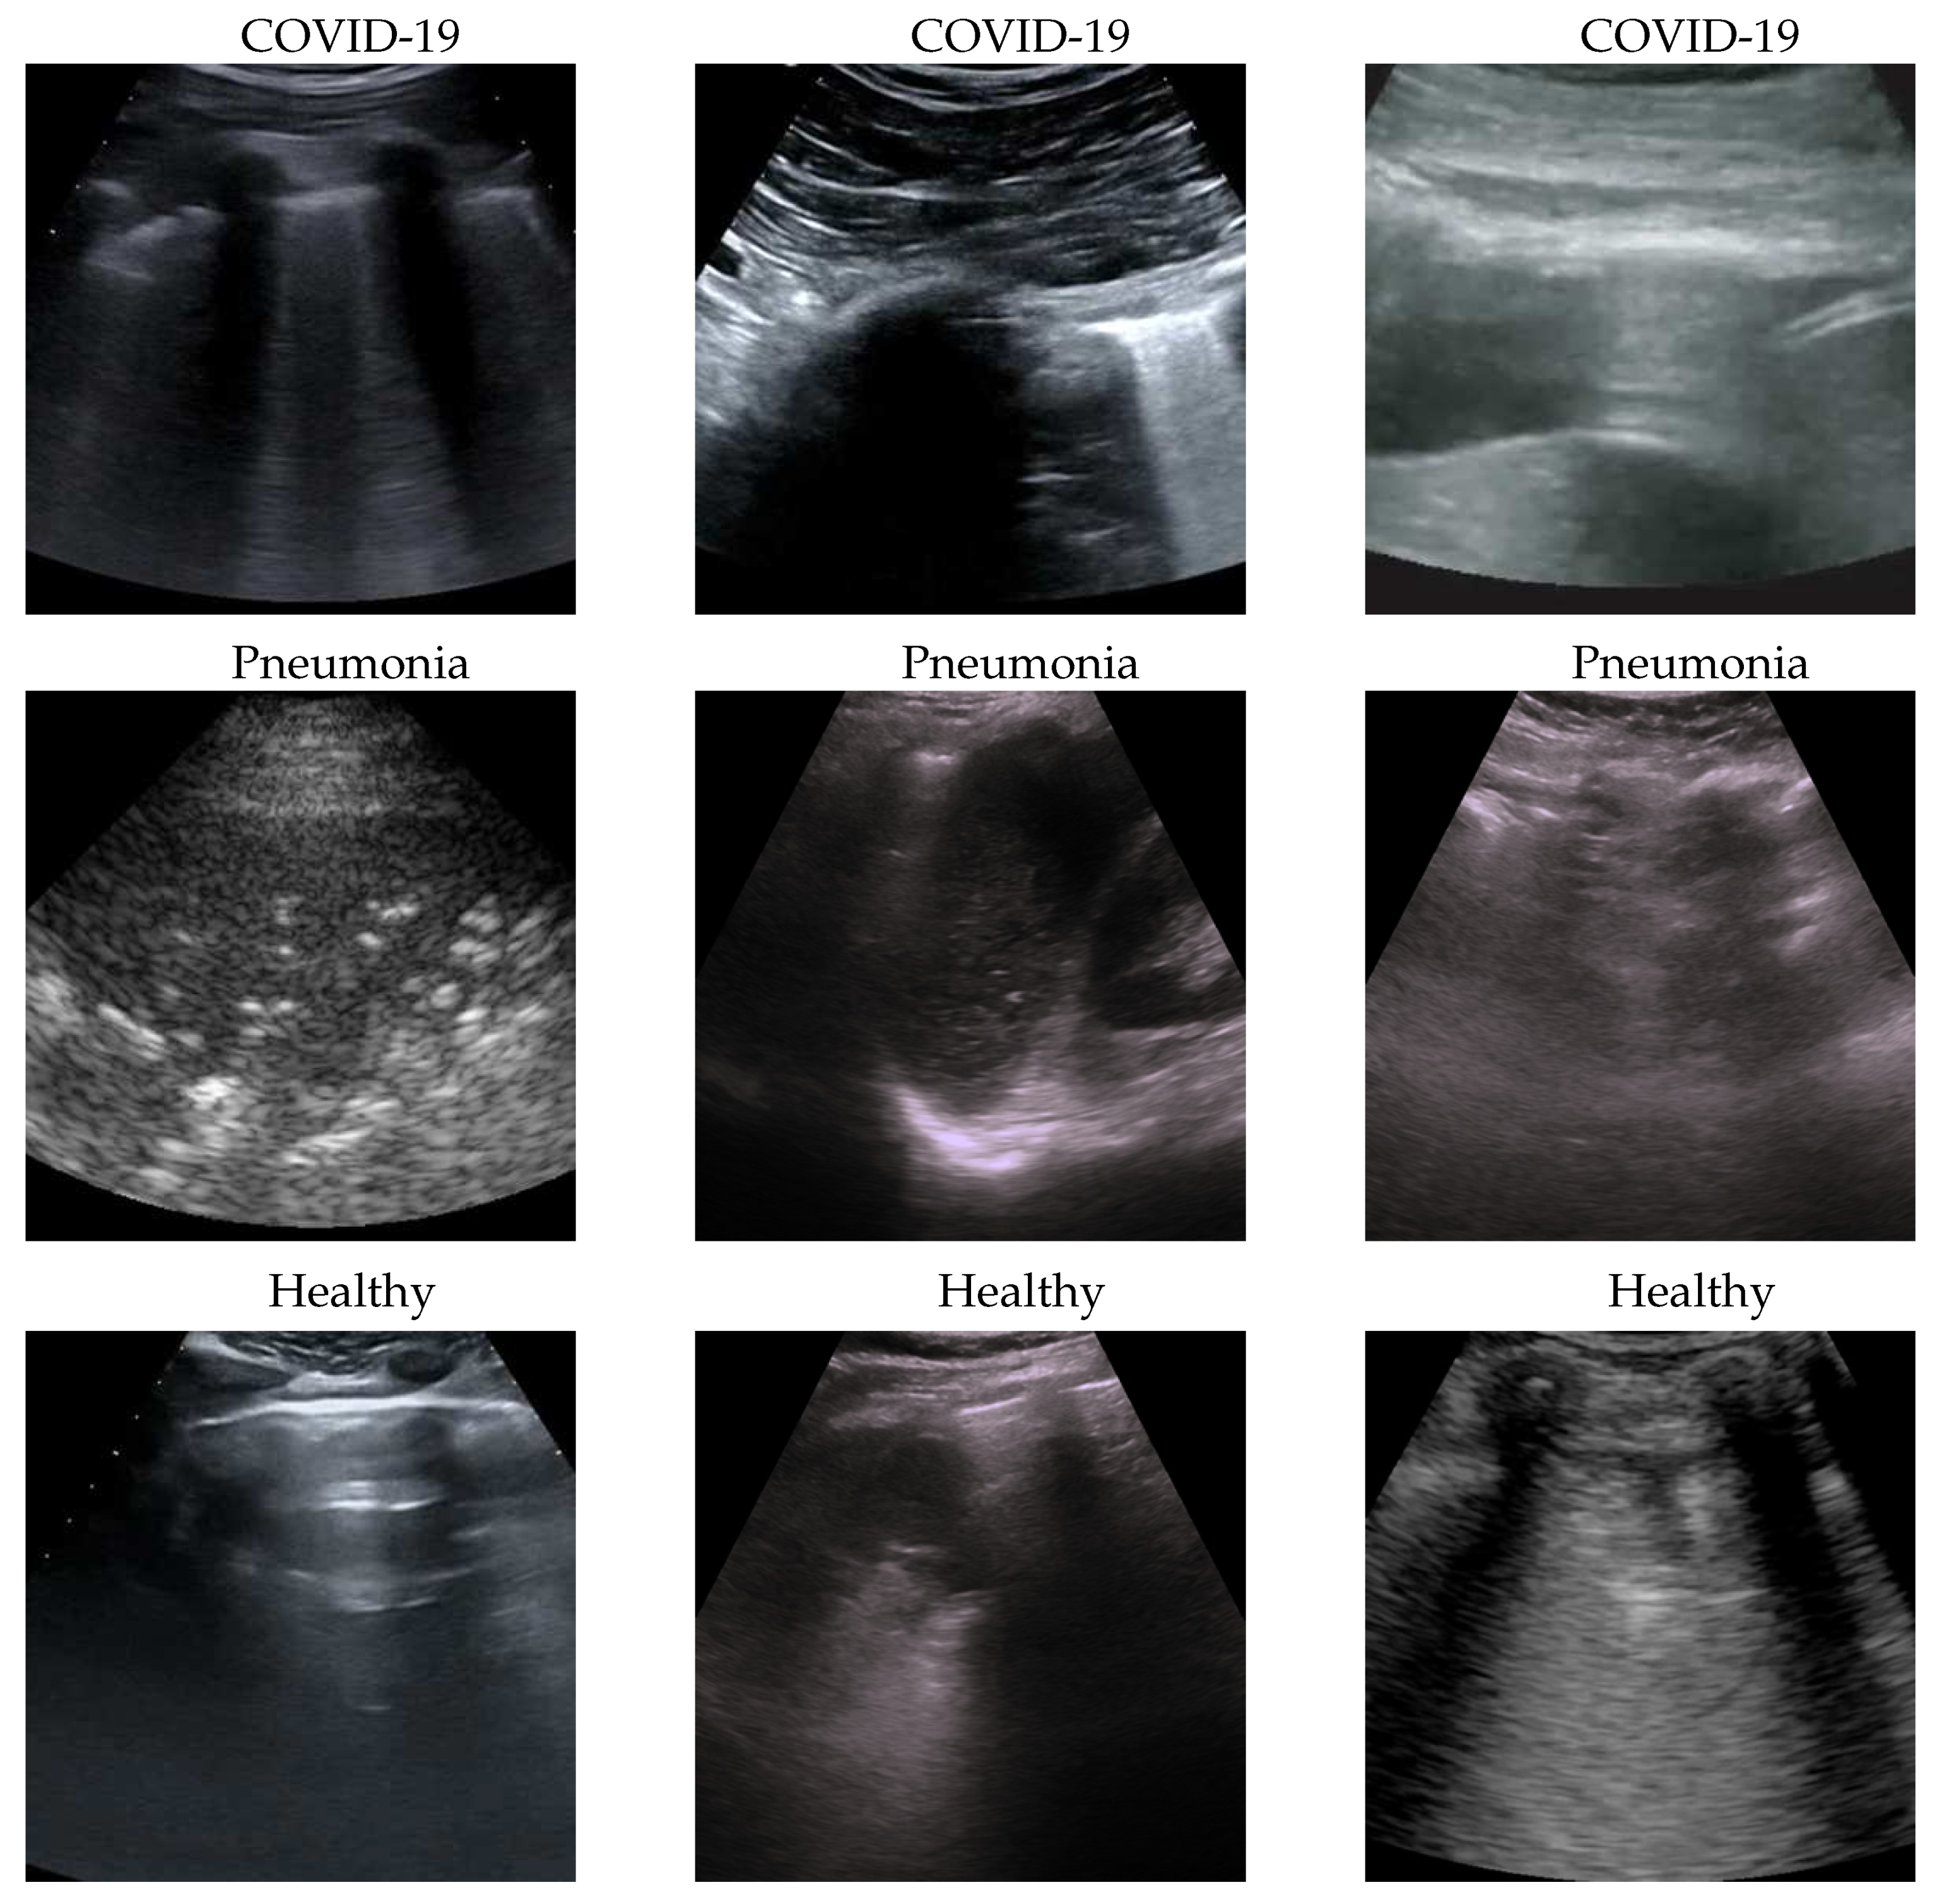

To better understand the behaviour of our model, we applied the Gradient-weighted Class Activation Mapping (GradCAM)[35] algorithm producing visual explanations: as the saliency maps show, our model seems to produce reasonable explanations since in all the cases it is focusing on meaningful areas. On the other side, when we apply the same method to weak models which didn’t obtain the 100% of accuracy, it is clear that the model concentrates on areas of the LUS that are less or not important. Indeed, we generally noticed that an accurate classification focus on (see a representative example in Figure 2):

• “evidence” usually at the upper side of the image and concentrated activations in case of COVID-19;

• “evidence” everywhere (mainly lower part) with relaxed activation in case of Pneumonia;

• mainly the healthy part of the lung (black) with very expanded activation in the case of Healthy.

Figure 2. Healthy (first row), Pneumonia (second row) and COVID-19 (third row) samples from the dataset and their saliency map. Red (higher) to blue (lower) scale.